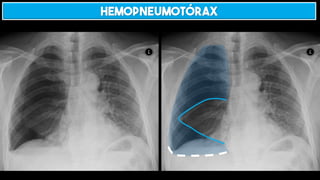

HEMOPNEUMOTÓRAX